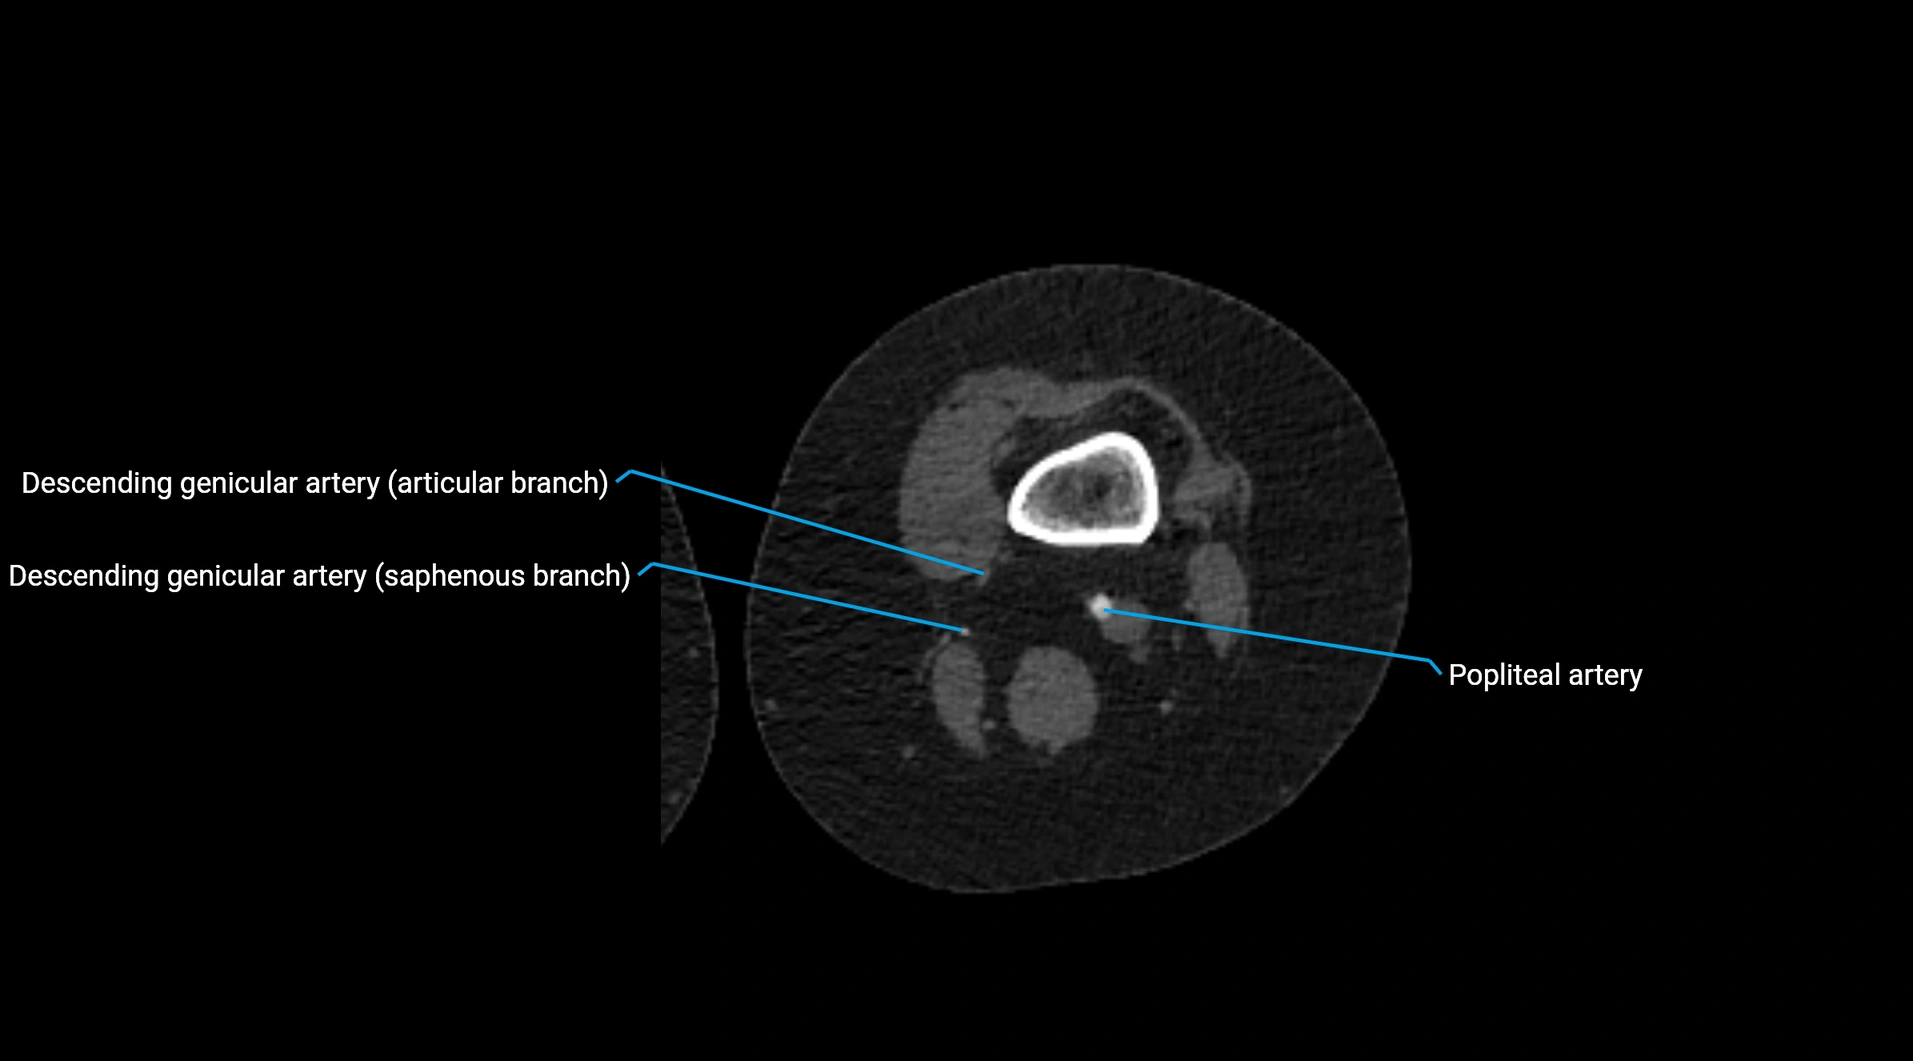

Contrast-enhanced CT (CTA):

• Gold standard for abdominal aortic imaging

• Provides excellent detail of lumen, wall, aneurysm, thrombus, and branch vessels

• Multiplanar and 3D reconstructions help in aneurysm measurement, stent graft planning, and dissection evaluation

• Detects acute rupture, traumatic injury, or occlusion with high sensitivity